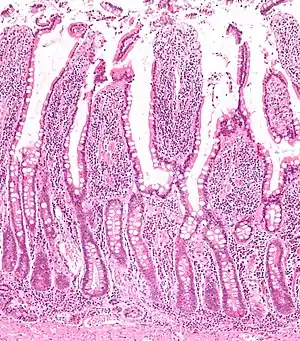

In histology, an intestinal gland (also crypt of Lieberkühn and intestinal crypt) is a gland found in between villi in the intestinal epithelium lining of the small intestine and large intestine (or colon). The glands and intestinal villi are covered by epithelium, which contains multiple types of cells: enterocytes (absorbing water and electrolytes), goblet cells (secreting mucus), enteroendocrine cells (secreting hormones), cup cells, tuft cells, and at the base of the gland, Paneth cells (secreting anti-microbial peptides) and stem cells.

Intestinal glands are found in the epithelia of the small intestine, namely the duodenum, jejunum, and ileum, and in the large intestine (colon), where they are sometimes called colonic crypts. Intestinal glands of the small intestine contain a base of replicating stem cells, Paneth cells of the innate immune system, and goblet cells, which produce mucus.[1] In the colon, crypts do not have Paneth cells.[2]